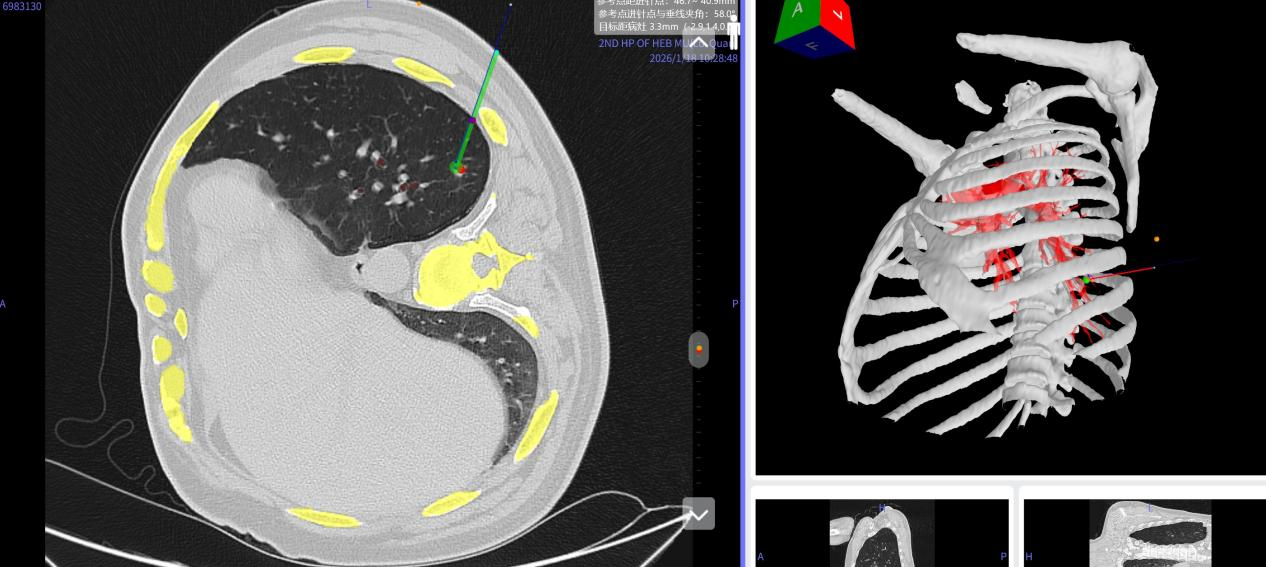

手术当日,患者接受全身麻醉后取侧卧位。李书军教授佩戴VR眼镜开始实施定位。在人工智能技术的驱动下,患者的肋骨、支气管、肺组织及血管等胸部结构,连同其呼吸动态,均以三维立体的形式实时呈现在视野中。

借助虚拟与现实融合的手术场景,医生将视线聚焦于患者病灶区域,通过调整视角精准锁定结节位置。随后手持一枚“伞形”三维标识定位穿刺标记物,依照系统导航提示,沿术前规划好的穿刺路径,精准避开肋骨与血管,将标记物顺利送达目标位置并释放。该“伞形”标记物采用自膨自锁的钝形设计,释放时可瞬时轻柔地推开周围组织与血管,不仅降低了出血风险,也实现了更稳固的锚定。整个定位过程仅用时不到5分钟。